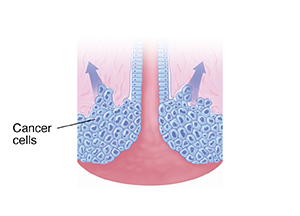

Invasive cancer occurs when abnormal cells spread. They move from the surface into deeper parts of the cervix. They may then spread to other areas of the body.